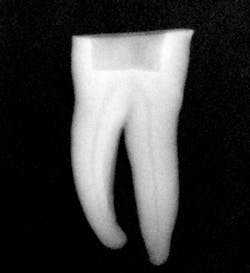

Figure 2: Radiograph confirming glide-path creation using SafeSider instruments.

After preparing straight-line access to the canal orifice (figure 1), explore the canal using small-sized instruments. I typically use a size 08 SafeSider by hand with the help of an apex locator to determine working length. I then use the SafeSiders in sizes 10, 15, and 20 to verify patency and confirm a smooth, reproducible glide path (figure 2). I always irrigate and enlarge the glide path to a minimum 20/02 preparation.